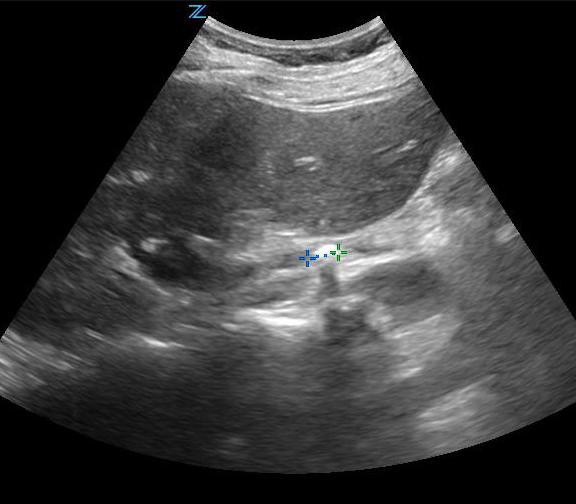

- Figure 1. Measurement of normal right kidney in longitudinal view

- Figure 2. Moderate hydronephrosis demonstrating location of ureter (surrounded by arrows) exiting renal pelvis